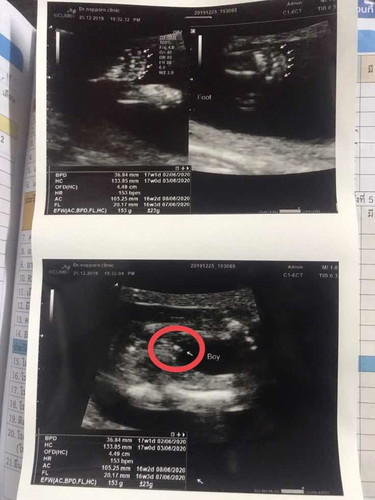

หมอบอกว่าเด็กผุ้ชายคับผม ตอนนี้16w เเม่ท้องเเรก เเม่ตัวเล็กสูง155 นน43 รกเกาะต่ำมาก ขอดูท้องเเม่ๆ16wหน่อยคะ??